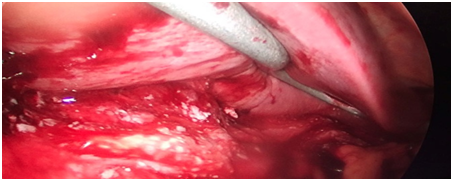

Figure 3 Intra operative Picture of caudate lobe liver abscess.

The patients were taken up for laparoscopic drainage as percutaneous approach was either not feasible (n=3) or failed (n=1). The patient was placed supine and general anesthesia was given with endotracheal intubation. Open access was used to gain access into peritoneal cavity. Three working ports were used. A Nathanson retractor was used to retract the left lobe of liver. Ports were placed in left and right hypochondrium in midclavicular line. The gastro hepatic omentum approach was followed. The location of abscess was confirmed intraoperatively with needle aspiration. The aspirate was sent for culture. Harmonic scalpel was used to enter the abscess cavity and create a wide window for drainage. The abscess was drained under vision. The cavity irrigated with copious amount of saline. An 18 F abdominal drain was placed in the abscess cavity under vision after irrigation and secured to the abdominal wall. The 10 mm port site was approximated with absorbable suture. The skin was approximated with skin clips. The intraoperative estimated blood loss was less than 100 ml in cases.